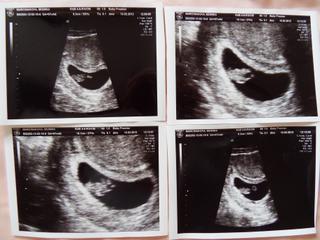

@nmonika...jeeej, presne taketo som na poslednom sone aj ja videla.Kolko meriate a zodpovedate aj velkostne podla PM?

Huraaa 🙂 takze vysetko za nami... a vse je OK! malinke ma skoro 3 cm, videla som normlane hlavicku, telicko, rucicky, nozicky 🙂 ..porod stanovili na cca 10.9. ... bola som sokovana ako sa tam to male metalo... normalna mini duracelka to je 😀

Strasne zvlastny pocit to vidiet.. zazrak.. 🙂 nechce sa mi verit ze sa mi v bruchu metá mini babetko 😀

@nmonika to je OK, mame podobny termin, ja som PM 18.12, na sone som bola 8+1, podla sona sme zodpovedali 7+6, a mali sme 1.5cm.. takze my sme este boli aj nejaky mensi troska.